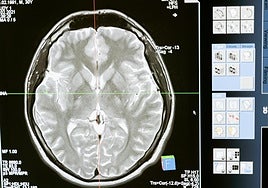

Tumores, infartos y problemas respiratorios, las principales causas de muerte en Jaén

Los casos de fallecimiento por Alzheimer se incrementan un 15% en el último trimestre de 2023 según el IECA, mientras el Covid sigue provocando decesos